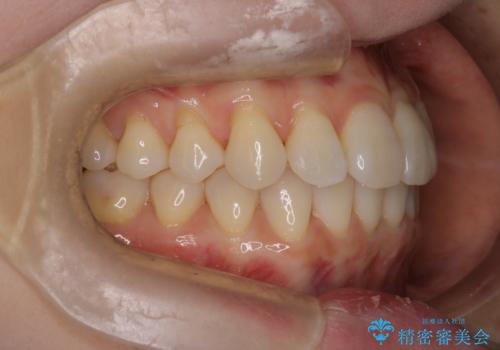

【インビザライン】かみ合わせを整えたい

- インビザラインで非抜歯治療を行いました。IPRと拡大をし、叢生、咬合をきれいにしました。

主訴であったかみ合わせを正しい位置に動かし、バランスよくかめるようになりました。矯正治療終了後にメタルインレーをセラミックインレーに替えました。